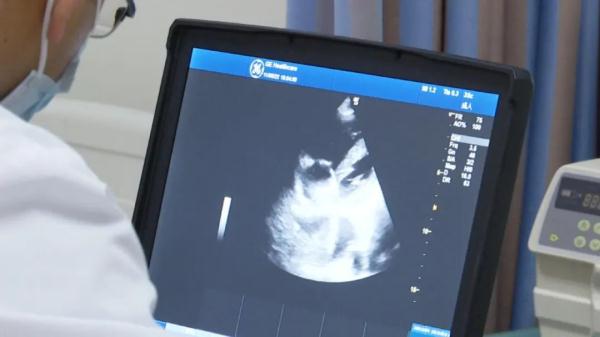

紧接着,医生为王先生进行了B超检查,进一步查看胸腔的情况,不出所料,导致王先生呼吸困难的原因,正是来自于胸腔里的大量积液。

医生对话患者家属:“胸腔积液了,就是个肺不张导致的呼吸困难,肺不张就是肺压缩掉了嘛,肺压缩气喘不上来,他还合并有感染的情况。”

医生介绍,导致胸腔积液的原因有很多,例如慢性心衰、肺部感染、肺结核或是肺部恶性肿瘤。

云南省第一人民医院急诊内科主治医师 裴文彬:“慢性的心衰导致胸腔积液一般是双侧,但是他的左侧并没有,所以可能还是考虑一些感染或者占位病变其它的病因导致的胸腔积液,在其它医院做过一些相关的检查,那时候其实高度怀疑是肺癌的可能性比较大,但是没有找到癌细胞。”